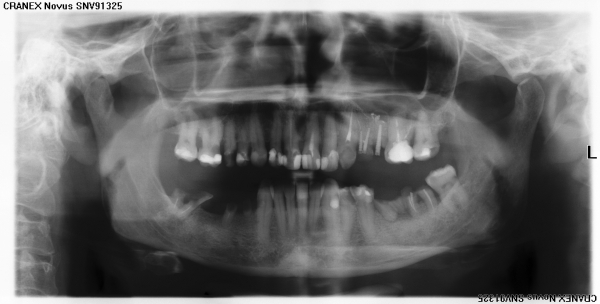

Мне необходимо протезирование. Можно ли по снимку сказать:

Скорее всего, оставшиеся корни на нижней и верхней челюсти порекомендуют удалить.

Восстановить дефекты зубного ряда можно имплантами.

На нижней челюсти возможно установление бюгельного протеза.

На передние зубы возможно установление керамических коронок.